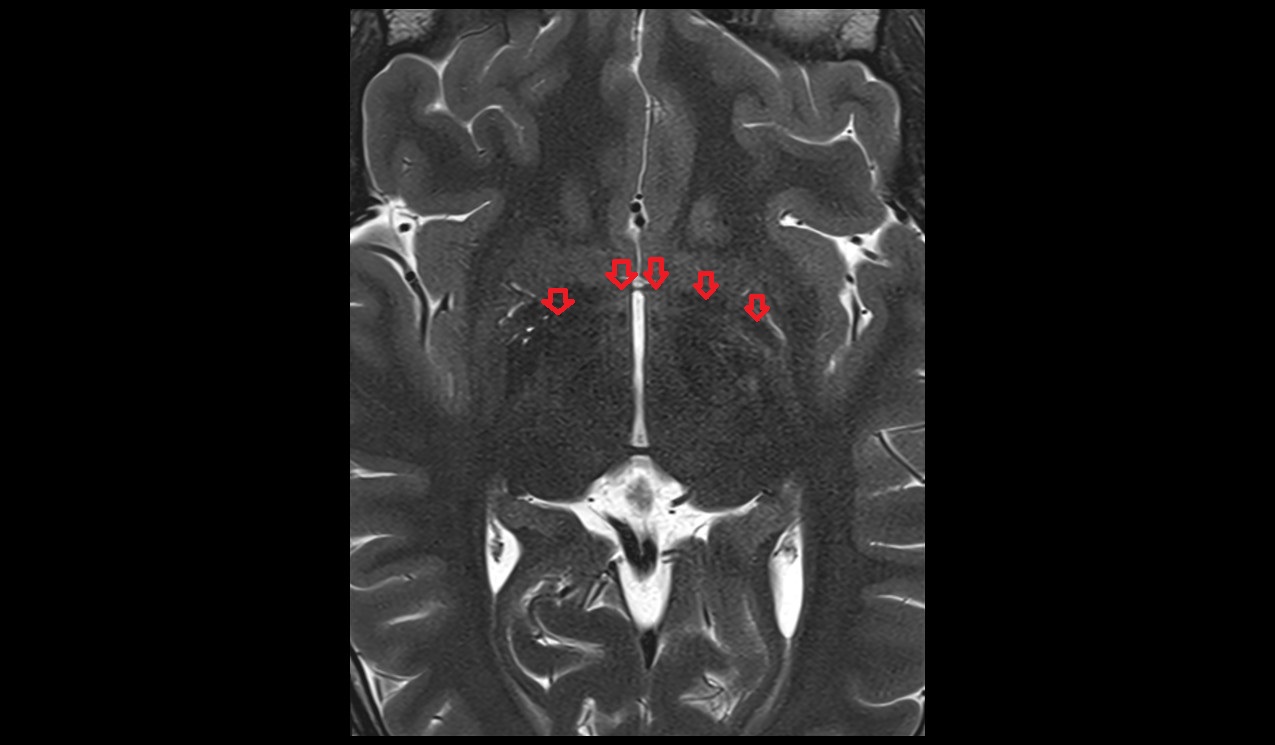

- Thalamus

- Interthalamic adhesion

- Head of caudate nucleus

- Body of caudate nucleus